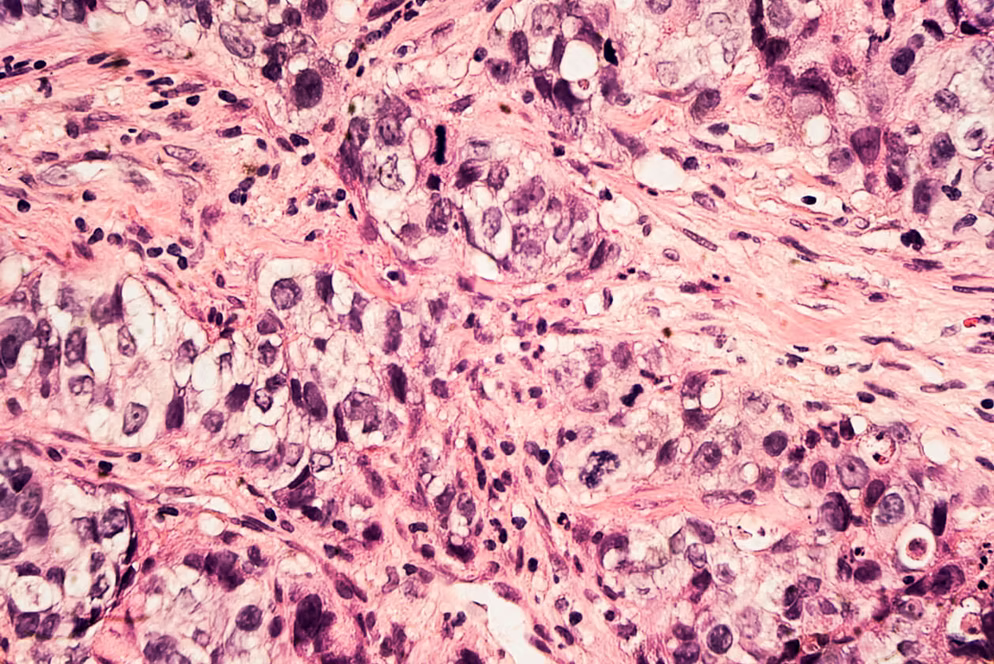

El cáncer de mama es uno de los tipos de cáncer más comunes entre las mujeres, pero gracias al diagnóstico temprano y a los tratamientos modernos, las tasas de curación aumentan cada año.

💉 MÉTODOS DE TRATAMIENTO PARA EL CÁNCER DE MAMA

El tratamiento depende del tipo y la etapa del cáncer, e incluye una o varias de las siguientes opciones: